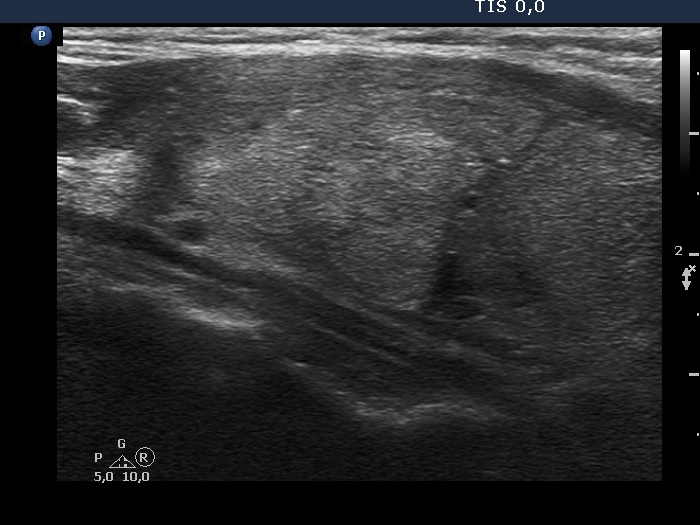

The borders of the nodule - case 2152 (ultrasonographic picture 7)

Upper part of the left lobe, longitudinal scan.